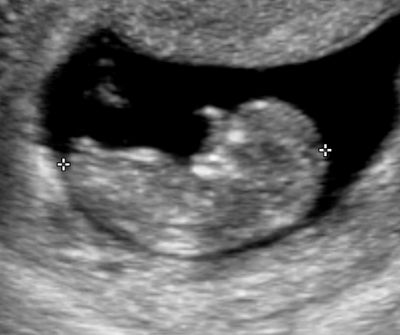

Embryon de 11 semaines d'aménorrhée.

Embryon de 12 semaines d'aménorrhée. La mesure de la clarté nucale doit se faire entre 11 semaines et 3 jours d'aménorrhée et 13 semaines et 3 jours.